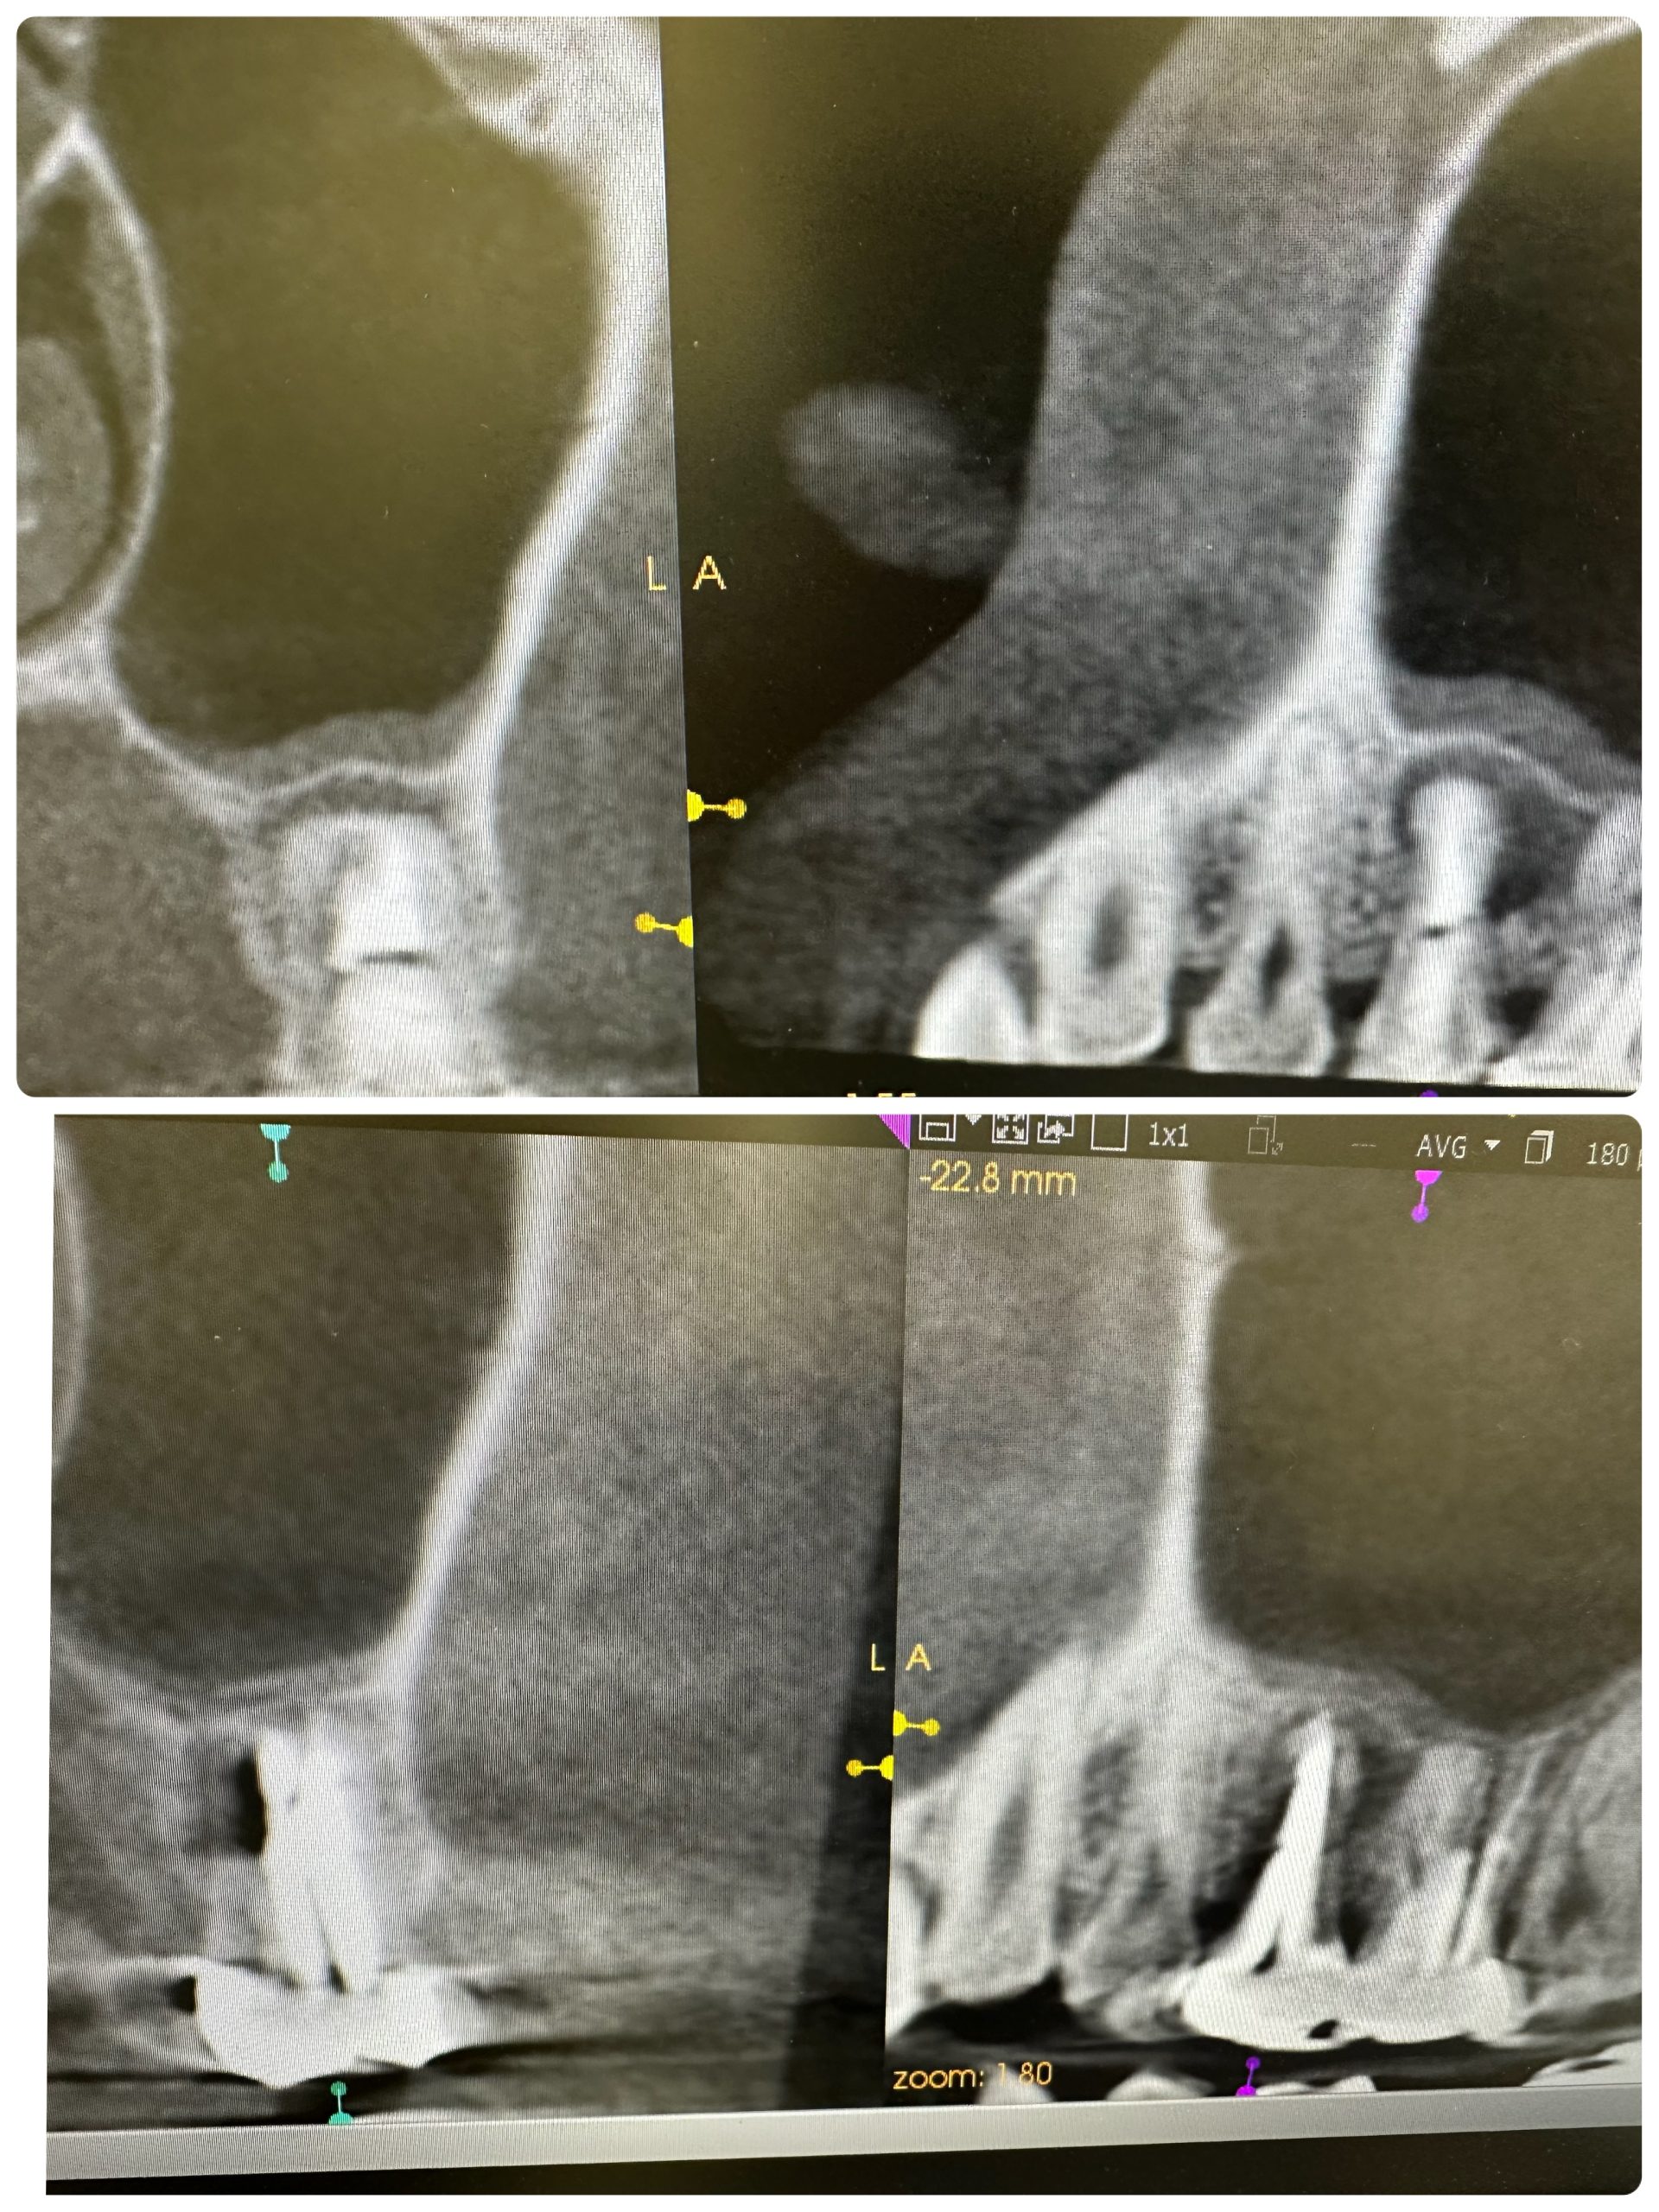

パラタルプレートの再生、ヤグレーザー併用の根管治療のみ

経過みないとね、自然治癒力は素晴らしい!

外科処置の勇み足にならない為の良い症例

最小侵襲で治癒導くが重要

CT撮影は、算定要件満たしてない為に無料😭

咀嚼に耐え得る歯は保存!